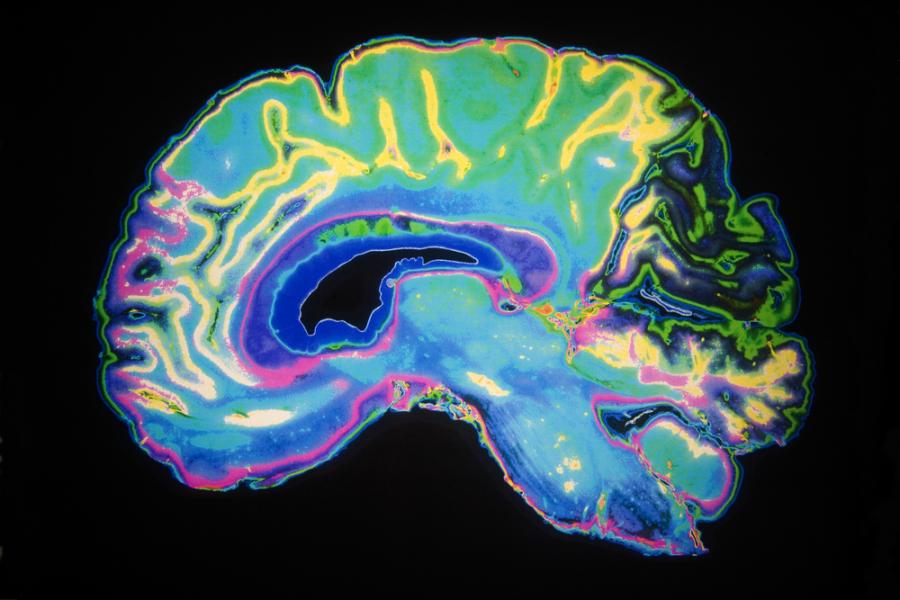

Учените откриват, че бадемовидното тяло нараства необичайно при бебета на възраст от 6 до 12 месеца, които впоследствие развиват аутизъм. Уголемяването продължава до 2-годишна възраст – моментът, в който родителите обикновено забелязват първите признаци на аутизма.

Бадемовидното тяло (наричано още амигдала) представлява набор от ядра в мозъка, разположени в тясно сътрудничество помежду си. То е част от лимбичната система, която е отговорна за регулиране на емоциите в отговор на неприятни гледки, усещания, миризми. Амигдалата най-често се свързва с емоции като страх и тревожност, както и с чувството на удоволствие в отрицателен смисъл, т.е. на агресия. Състояния като гняв, отбягване и определени защити се активират именно благодарение на нея. Тя е отговорна и за задействането на наследствените признаци на стреса.